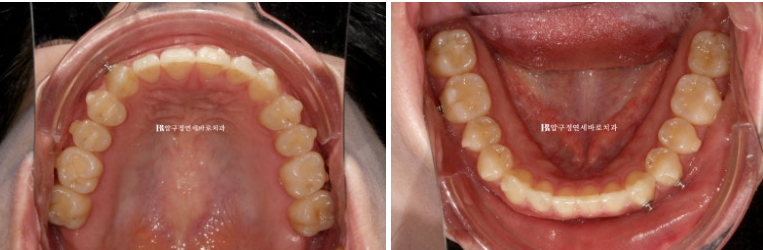

24.06

배열과 덧니는 가지런해졌습니다.

중심선 개선은 아직 미미합니다.

우측에 II급 고무줄을 열심히 걸어서 교합관계가 조금은 좋아졌습니다.

좋아진 배열과 옥니입니다.

우측 어금니 교합관계를 악간고무줄로 좀 더 개선하고 앞니 각도 역시 좀 더 세우고 싶어서 추가제작에 들어갔습니다.